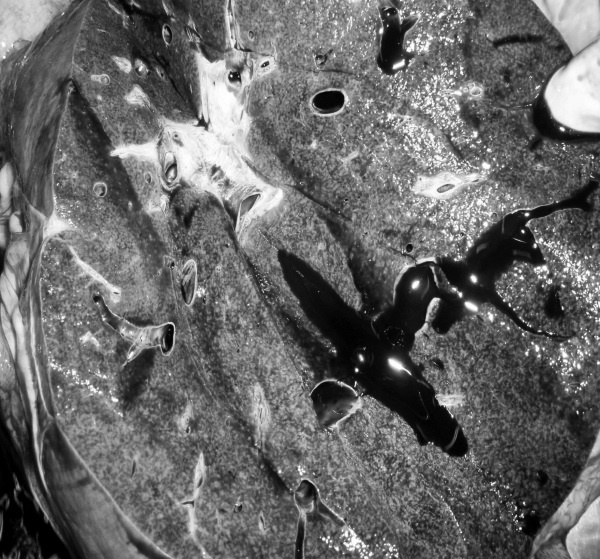

В посмертном эпикризе указан Основной диагноз: последствия ОНМК от 2008 года. ИБС. СН 2. ПИКС. Фоновое: СД 2-го типа, сопутствующее: хронический пиелонефрит. Осложнения: внебольничная пневмония. На секции: ![]() Рис. 31. Последствия перенесенного ОНМК ![]() Рис. 32. Атеросклероз церебральных артерий ![]() Рис. 33. Постинфарктный кардиосклероз ![]() Рис. 34. Гипертрофия миокарда левого желудочка ![]() Рис. 35. Признаки ХСН: мускатный фиброз печени ![]() Рис. 36. Пневмония ![]() Рис. 37. Признаки хронического пиелонефрита Анализируя данный клинический пример, необходимо отметить следующее. 1. Социальный статус. Социальный статус, за исключением указания на участие в ВОВ, не обозначен. 2. Наблюдение на дому. Полное несоблюдение регламента наблюдения ДИП. Клинический диагноз. Записи в амбулаторной карте нет. При этом диагноз должен быть следующим. Основной: последствия ОНМК от 2008 года. ИБС. Постинфарктный кардиосклероз. Фоновое: гипертоническая болезнь 3-й ст., 3 ст. риск 4. СД 2-го типа. Осложнения: длительная иммобилизация. Внебольничная пневмония. НК 2. Хронический пиелонефрит. Анемия. 3. Обоснованность назначения лекарственных препаратов. Терапия СД проводилась вне соответствия с клиническими рекомендациями, контроль за уровнем гликемии не осуществлялся, лечение анемии отсутствовало, вместе с тем при отсутствии подтвержденных данных за пиелонефрит были назначены антибиотики. Таким образом, наряду с указанными замечаниями врач не оценил тяжесть состояния, что не позволило решить вопрос о показанной госпитализации. Приложение № 6 – алгоритм лечения анемии. Приложение № 7 – самоконтроль уровня глюкозы. Пациентка Ф., 84 года. Умерла в январе 2011 года. Иммобилизирована с марта 2010 года в связи с закрытым переломом лонной и седалищной костей. В карте ежемесячные осмотры терапевта в связи с активами СМП. Причина вызовов: гипертонические кризы и болевой синдром. За год до смерти проведены доступные на дому анализы. В плановом порядке в апреле 2010 году проходила стационарное лечение в терапевтическом отделении. Диагноз при выписке: дисциркуляторная энцефалопатия 2-й ст. ГБ. ИБС. СН 3. ПИКС от 2001 года. Железодефицитная анемия. Закрытый перелом лонной и седалищной костей справа. Амбулаторно после стационара принимала энап Н и винпоцетин. В посмертном эпикризе указан Основной диагноз: 1) дисциркуляторная энцефалопатия 2-й ст. и ИБС. СН 3. ПИКС от 2001 г. НК 2А. Фоновое: ГБ. Сопутствующее: хроническая железодефицитная анемия. Закрытый перелом лонной и седалищной костей от 11.03.2010. ![]() Рис. 38. Повторный инфаркт головного мозга ![]() Рис. 39. Постинфарктный кардиосклероз ![]() Рис. 40. Атеросклероз коронарных артерий ![]() Рис. 41. Проявления НК: мускатный фиброз печени ![]() Рис. 42. Острые эрозии желудка ![]() Рис. 43. Атеросклероз аорты Замечания к ведению больного следующие: 1. Социальный статус. Информации нет. 2. Наблюдение на дому. Посещение терапевта осуществлялось только в связи с активами СМП. 3. Клинический диагноз. Нет правильной формулировки диагноза. При этом правильный диагноз был бы следующим. Основной диагноз: 1) Повторный инфаркт головного мозга. 2) ИБС. Постинфарктный кардиосклероз от 2001 года. Фоновое: гипертоническая болезнь 3 ст., 3 ст. Осложнения: закрытый перелом лонной и седалищной костей от 11.03.2010. Длительная иммобилизация. НК 2. Острые эрозии. Хроническая железодефицитная анемия. Сопутствующие: атеросклероз аорты. 4. Обоснованность назначения лекарственных препаратов: лекарственная монотерапия ГБ эналаприлом неэффективна, что повлекло за собой неоднократные гипертонические кризы и вызовы СМП, нет лечения проявлений ПИКС и анемии. Таким образом, не было оценки тяжести состояния, наличия тяжелой степени АГ у больной с перенесенным ОНМК и инфаркта миокарда, кризовым течением и признаками СН, что требовало госпитализации пациента. Приложение № 8 – ведение больного, перенесшего инфаркт миокарда. Пациентка Б., 95 лет. Иммобилизирована. Карта малоинформативна. Осмотры терапевта 1–2 раза в год, лист впервые выявленных диагнозов не ведется. Анализы отсутствуют. Известно, что наблюдалась с диагнозом ИБС, ЦВБ. Хронический бронхит. ОНМК с левосторонним гемипарезом и перелом шейки бедра без указания давности. В карте имеются указания на пролежни. За последние 2 года до смерти терапевтом были назначены: пирацетам, предуктал, мексидол, проведен курс ЛФК на дому. Посмертный эпикриз отсутствует. На секции: ![]() Рис. 44. Последствия перенесенного инфаркта головного мозга ![]() Рис. 45. Постинфарктный кардиосклероз |